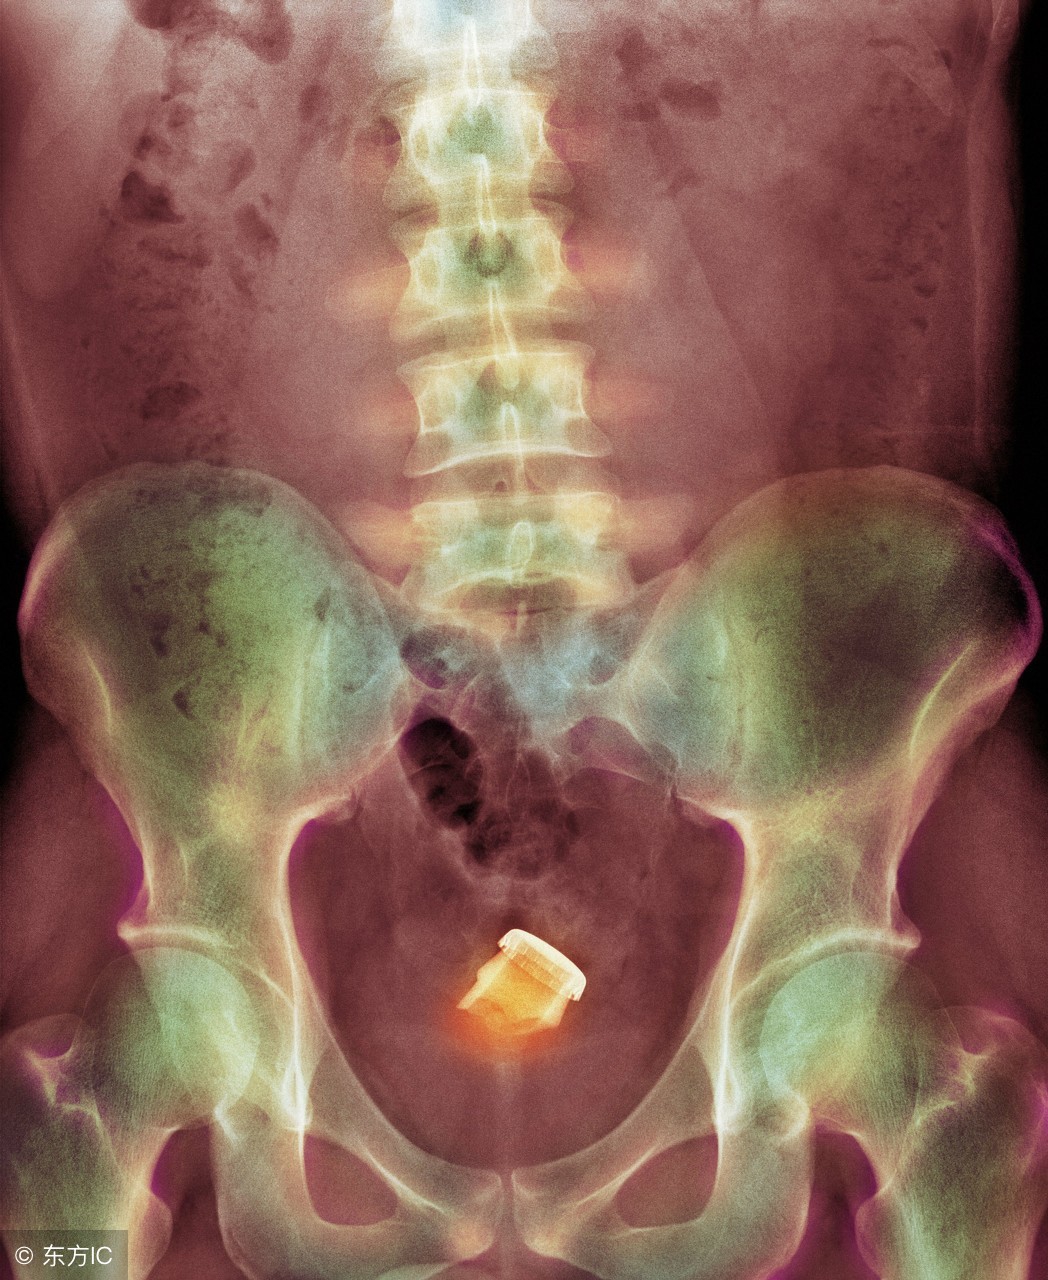

误食或者不小心吞食的物品(比如弹珠等小玩具),因为无法被肠胃消化,刚好停留在肛门直肠交界处或之上;胆结石或者粪石等嵌顿在直肠上;人为插入直肠的物品等都被称为直肠异物。

当然,并不是所有的异物都能用上述方法取出,当所有办法都不奏效时,就只能开腹取出。这种情况一般都要做造瘘口,创伤很大,而且还会挂个粪袋,以便接受排泄物。